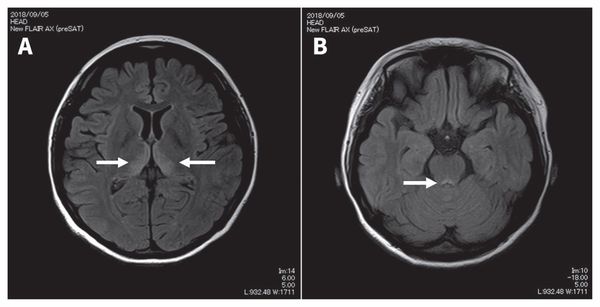

Наиболее эффективный метод диагностики энцефалопатии Вернике — это МРТ. Интерпретировать результаты МРТ сможет только врач.

![Признаки энцефалопатии Вернике на снимке МРТ [22]](/pimg3/pechenochnaya-entsefalopatiya-prichini-C1650F.jpeg)